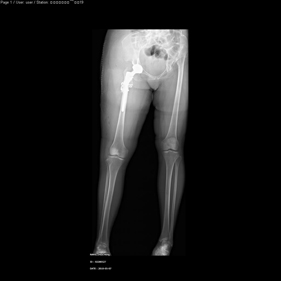

- Bone transport

shortening osteotomy and total hip replacement for bilateral severe dysplasia of hip with high riding